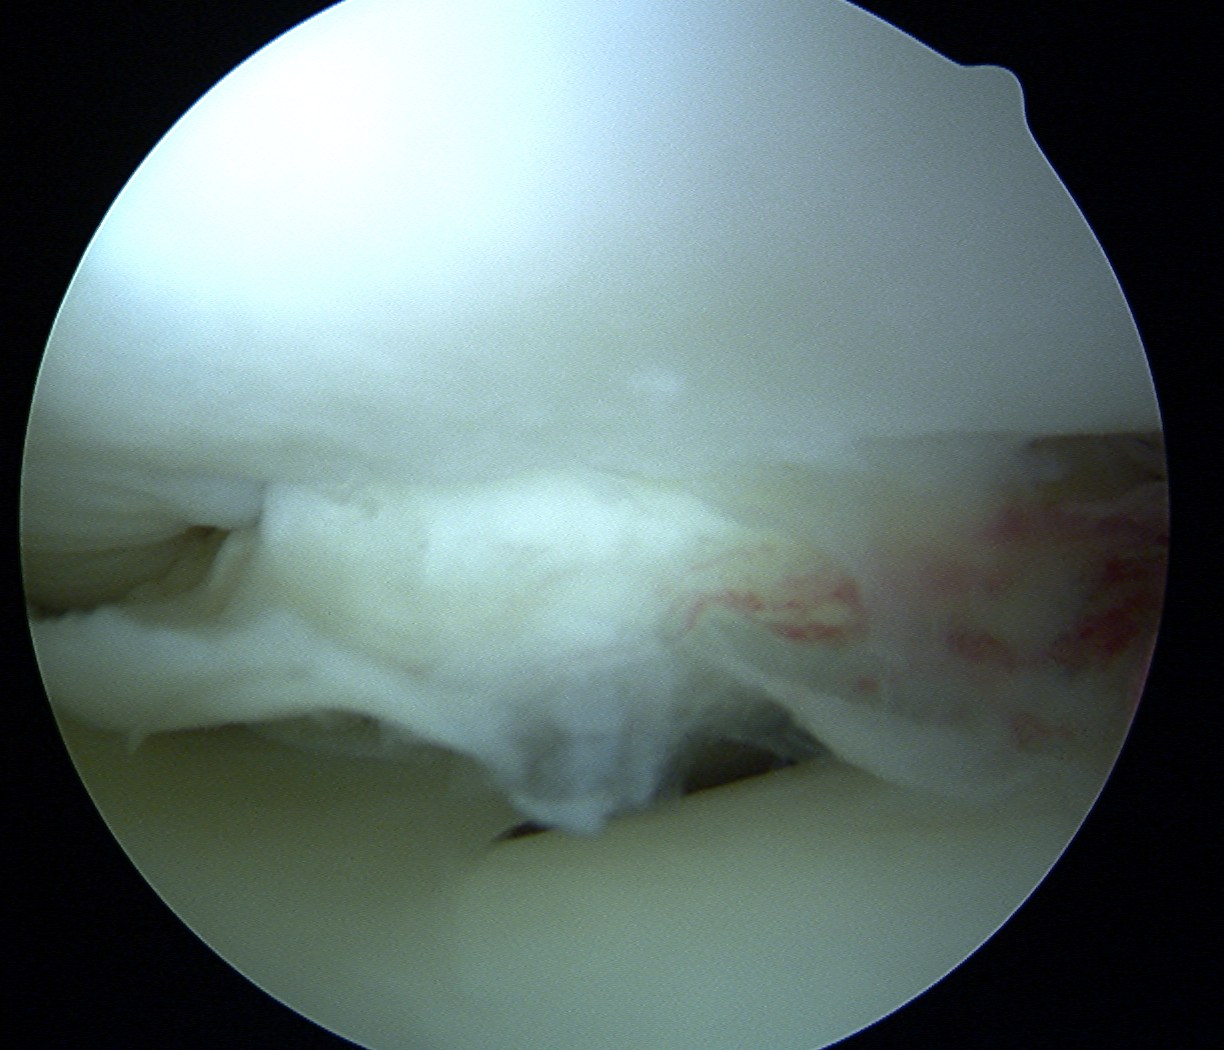

Technique Mosaicplasty Type 3 OCD

Harvest

- insert 4.5 mm chisel

- hammer to appropriate depth / 20 mm

- twist handle to remove

Debride base of OCD and reduce